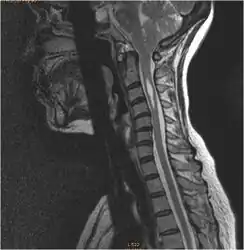

Syringomyelia

Syringomyelia is a chronic progressive degenerative disorder characterized by a fluid-filled cyst located in the spinal cord. Its symptoms include pain, weakness, numbness, and stiffness in the back, shoulders, arms or legs. Other symptoms include headaches, the inability to feel changes in the temperature, sweating, sexual dysfunction, and loss of bowel and bladder control. It is usually seen in the cervical region but can extend into the medulla oblongata and pons or it can reach downward into the thoracic or lumbar segments. Syringomyelia is often associated with type I Chiari malformation and is commonly seen between the C-4 and C-6 levels. The exact development of syringomyelia is unknown but many theories suggest that the herniated tonsils in type I Chiari malformations cause a "plug" to form, which does not allow an outlet of CSF from the brain to the spinal canal. Syringomyelia is present in 25% of patients with type I Chiari malformations.[10]

Diagnosis is made through a combination of patient history, neurological examination, and medical imaging.[14] Magnetic resonance imaging (MRI) is considered the preferred imaging modality for Chiari malformation.[15] The MRI visualizes neural tissue such as the cerebellar tonsils and spinal cord as well as bone and other soft tissues. CT and CT myelography are other options and were used prior to the advent of MRI, unfortunately the resolution of CT based modalities do not characterize syringomyelia and other neural abnormalities as well.